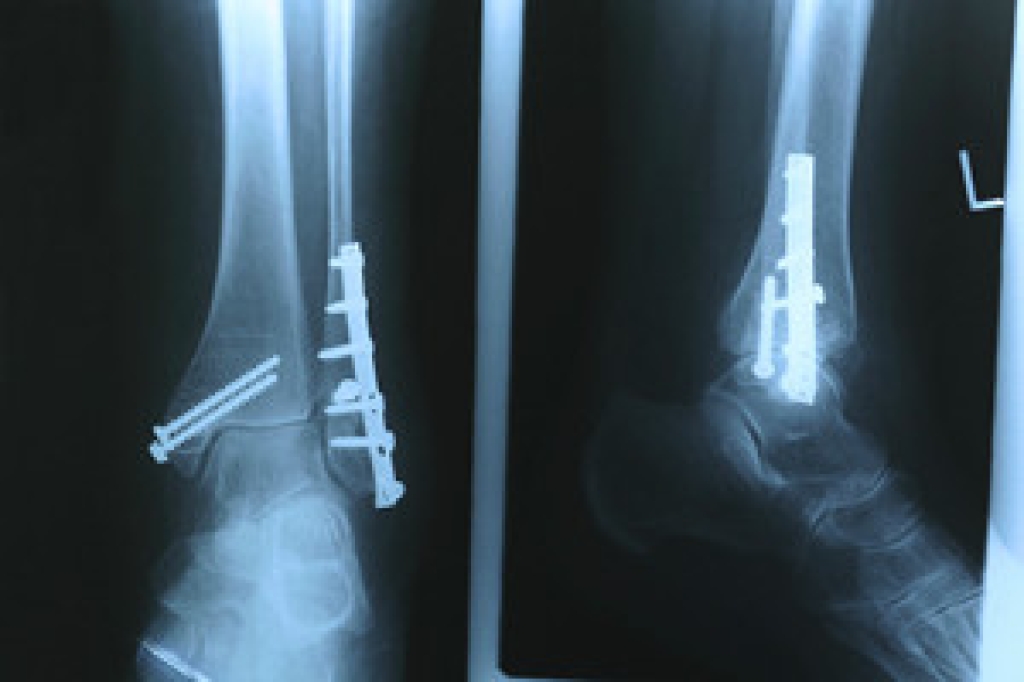

A fractured ankle can significantly disrupt daily life, particularly impacting employment. This type of injury often requires an extended period of immobilization, followed by a lengthy rehabilitation process to restore full functionality. The inability to walk or stand for prolonged periods can make it challenging to perform job duties, especially in physically demanding roles. Consequently, high rates of unemployment and disability are observed among those with severe ankle fractures. The disruption stems from the need for rest and restricted movement to ensure proper healing, which can lead to extended absences from work. Additionally, the pain and swelling associated with a fractured ankle can hinder mobility and productivity. Without adequate treatment and rehabilitation, complications such as chronic pain, instability, and arthritis may develop, further delaying recovery and complicating return-to-work plans. If you have suffered an ankle fracture, it is strongly suggested that you receive a comprehensive treatment plan from a podiatrist to recover efficiently and return to work as quickly as possible.

Broken ankles need immediate treatment. If you are seeking treatment, contact Frederick Matthews, DPM from Innovative Foot and Ankle Care. Our doctor can provide the care you need to keep you pain-free and on your feet.

Broken Ankles

A broken ankle is experienced when a person fractures their tibia or fibula in the lower leg and ankle area. Both of these bones are attached at the bottom of the leg and combine to form what we know to be our ankle.

When a physician is referring to a break of the ankle, he or she is usually referring to a break in the area where the tibia and fibula are joined to create our ankle joint. Ankles are more prone to fractures because the ankle is an area that suffers a lot of pressure and stress. There are some obvious signs when a person experiences a fractured ankle, and the following symptoms may be present.